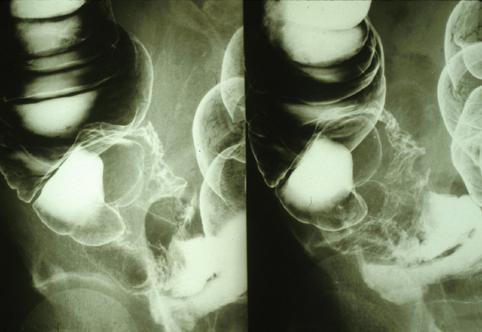

疾病(病理主体)的分类其他肿瘤/恶性阑尾粘液肿瘤

部位(按器官分)大肠/阑尾

检查方法X线

肿瘤最大直径40以上